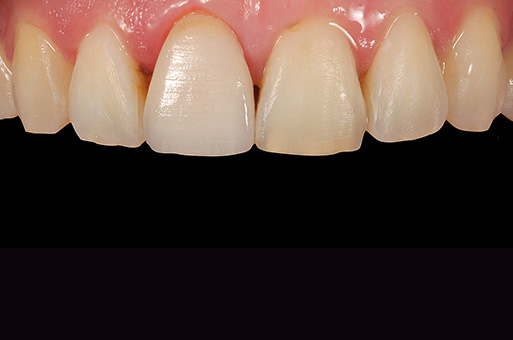

Situation initiale

Suite à un traumatisme, les 11 et 21 avaient fait l'objet de restauration en composite qui dataient maintenant de plusieurs années. La patiente n'était pas satisfaite de l'esthétique de ces deux dents, dont elle n'appréciait ni la couleur ni la forme. Elle souhaitait les faire refaire depuis un certain temps déjà.

Solution

Après analyse des dents antérieures et de la zone esthétique, il a été proposé à la patiente de restaurer non seulement les 11 et 21, mais simultanément aussi les 12 et 22, légèrement inclinées en palatin, afin d'obtenir un meilleur résultat esthétique global. Le traitement a été planifié et réalisé à l'aide d'une maquette. Le choix s'est porté sur quatre facettes en céramique feldspathique à structure fine polychrome VITABLOCS TriLuxe forte 1M2, très esthétique.

Pourquoi VITABLOCS TriLuxe forte ?

Nous avons utilisé VITABLOCS TriLuxe forte parce que les blocs intègrent un gradient chromatique naturel ainsi que des effets lumineux et fluorescents. Au design CAO, les facettes ont déjà pu être façonnées morphologiquement comme prévu dans le wax-up analogique. La macrotexture a également été prise en compte, de sorte qu'après l'usinage des restaurations en céramique feldspathique à structure fine, il ne restait plus qu'à intégrer de petits détails de la microtexture. Après la finition, la caractérisation et le glaçage ont été minimes. Les VITABLOCS TriLuxe forte permettent de réaliser des restaurations tout à fait esthétiques avec un minimum d'efforts.

À l'aide d'une maquette, on a procédé de manière planifiée et la préparation a été effectuée de manière peu invasive.

Préparation peu invasive des 11 et 21 avant la pose des facettes.

L'émail a été mordancé à l'acide phosphorique afin d'obtenir une surface micro-rétentive.

Pose entièrement adhésive de la facette sur 21 avec VITA ADIVA F-CEM.

L'arcade dentaire harmonisée vue latéralement.

Les VITABLOCS TriLuxe forte ont permis de réaliser des restaurations très esthétiques avec un minimum d'efforts.